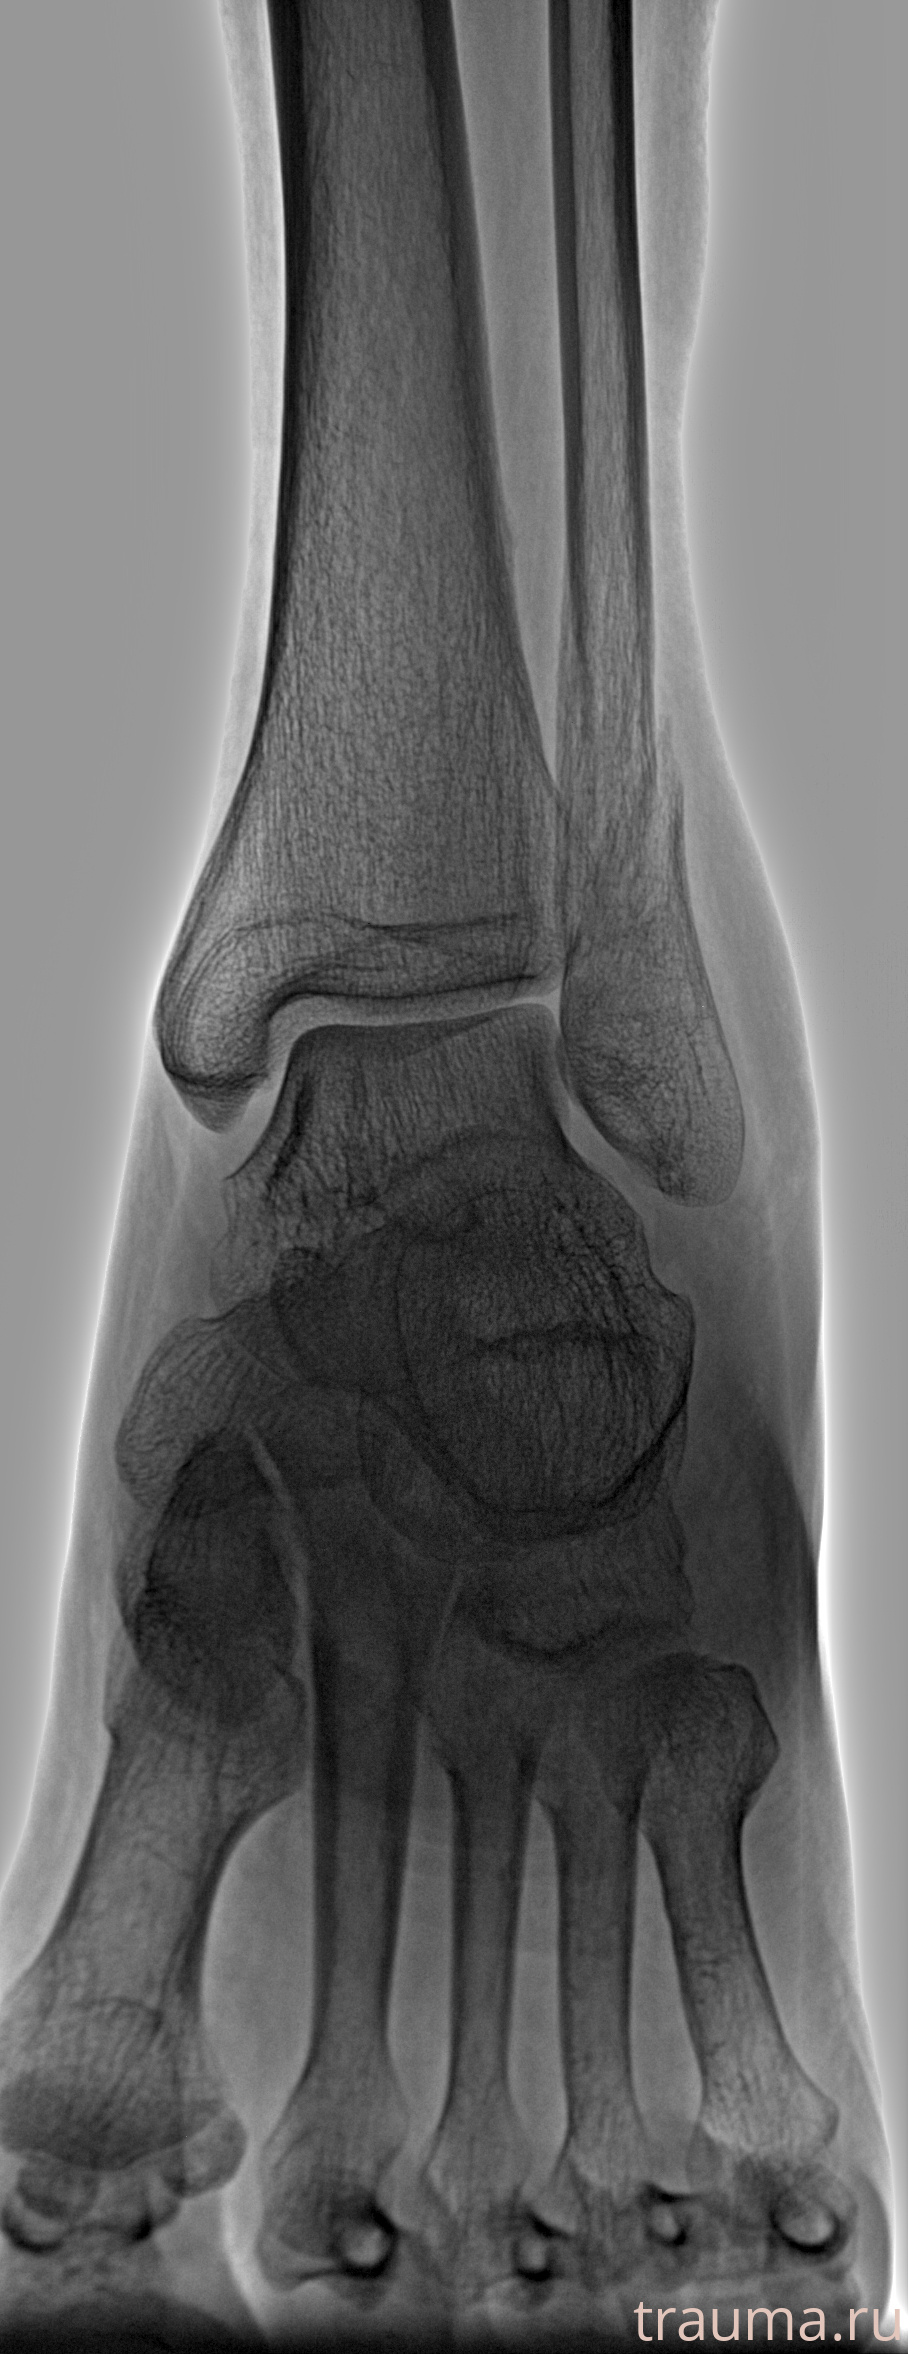

Рентгенограммы

Рентген на дому: по вашему адресу приезжает врач-рентгенолог, травматолог-ортопед с мобильным рентгеновским аппаратом, проводит диагностику травмы или заболевания, делает необходимые рентгенограммы, дает рекомендации по дальнейшему лечению. Получить качественные снимки в домашних условиях возможно благодаря уникальной методике, разработанной МосРентген Центром для института  Склифосовского

Яркость: 1   Контраст: 1   Инвертировать: 0 Увеличение: 1

Перетаскивайте мышь вверх/вниз для контраста, влево/право для яркости. Прокрутка колесом изменяет масштаб. Нажмите Сбросить для возврата к исходному изображению. При увеличении держите мышь в той области, которую хотите рассмотреть.